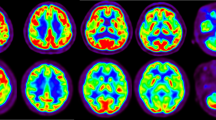

Movement impairments in Parkinson’s disease (PD) are caused by the degeneration of dopaminergic neurons and the consequent disruption of connectivity in the cortico-striatal-thalamic loop. This study evaluated brain metabolic connectivity in a 6-Hydroxydopamine (6-OHDA)-induced mouse model of PD using 18F-fluorodeoxy glucose positron emission tomography (FDG PET). Fourteen PD-model mice and ten control mice were used for the analysis. Voxel-wise t-tests on FDG PET results yielded no significant regional metabolic differences between the PD and control groups. However, the PD group showed lower correlations between the right caudoputamen and the left caudoputamen and right visual cortex. Further network analyses based on the threshold-free persistent homology framework revealed that brain networks were globally disrupted in the PD group, especially between the right auditory cortex and bilateral cortical structures and the left caudoputamen. In conclusion, regional glucose metabolism of PD was preserved, but the metabolic connectivity of the cortico-striatal-thalamic loop was globally impaired in PD.

Assessment of regional metabolic differences between the PD and control groups

On visual analysis, there was no significant difference between FDG PET images of PD and control group (Supplementary Fig. 3a). Also in the voxel-wise analysis, there were no significant regional metabolic differences between the PD group and the control group, using a false discovery rate (FDR)-corrected p < 0.05. Using a lenient criterion of uncorrected p < 0.001, the PD group tended to display regional hypometabolism in the right caudoputamen (AP:0.3 mm, ML:1.6 mm, DV:2.1 mm, apart from bregma) and right somatosensory cortex (AP:0.9 mm, ML:2.9 mm, DV:2.5 mm, apart from bregma) (Supplementary Fig. 3b).